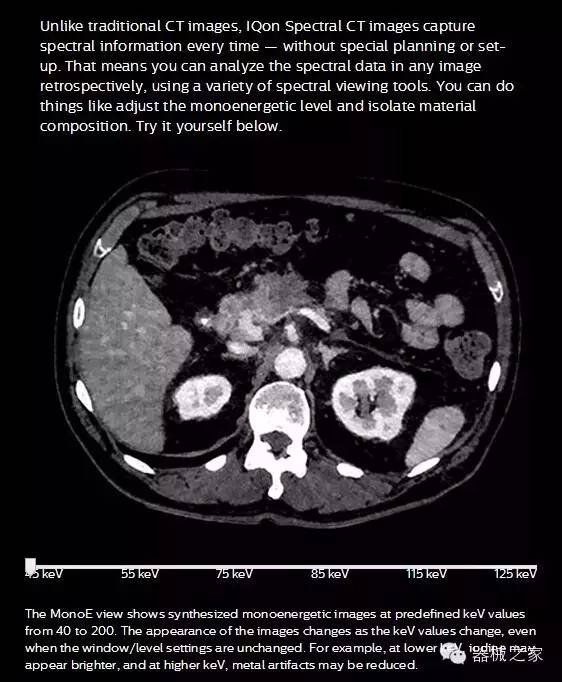

IQon光谱CT能够按照需求提供光谱量化和工具,并能通过简单工作流程、在低剂量下对结构进行定性分析

IQon光谱CT -- 是业界首台以探测器为成像基础的光谱CT,它可以在单次常规扫描下获得传统解剖影像及光谱功能影像。不仅可以提供精准的诊断信息,还可简化工作流程、在低剂量下完成定量与定性分析。